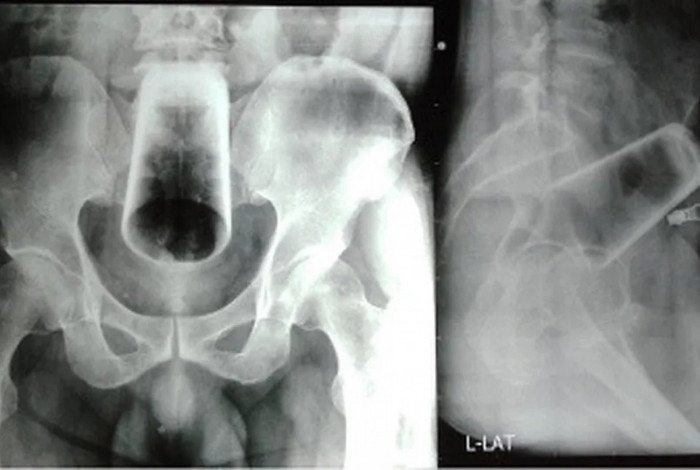

Exame de radiografia mostra a imagem do copo de vidro inserido no intestino de um homem nepalêsReprodução/Journal of the Nepal Medical Association

As imagens da radiografia, que viralizaram nas redes sociais, mostraram que o copo estava em posição invertida. Após o fracasso no procedimento manual de remoção, os médicos optaram pela cirurgia, com uma incisão no intestino, para evitar o risco de o copo de vidro quebrar.